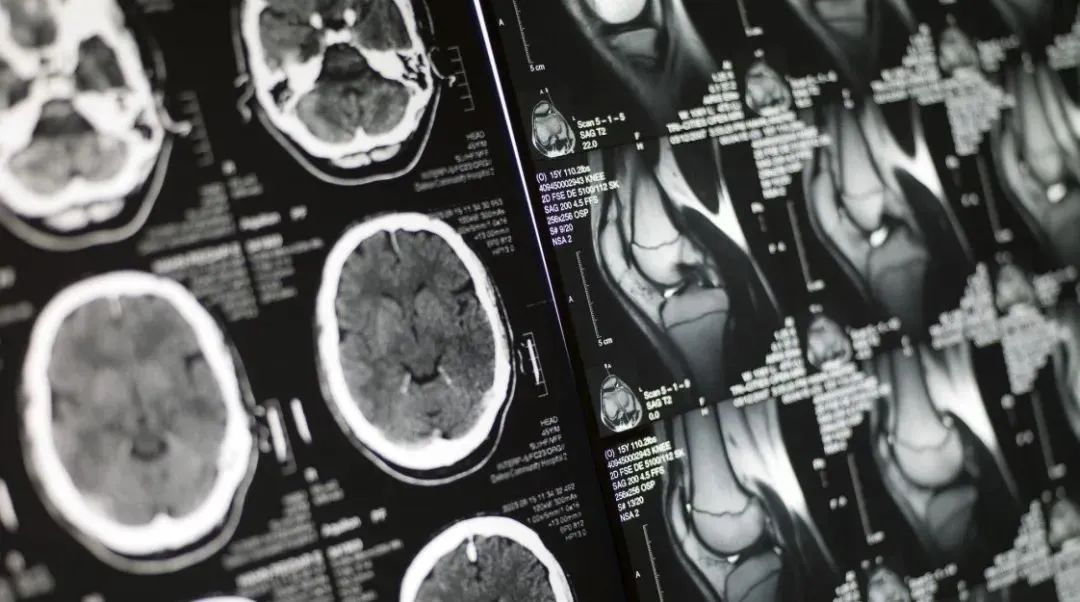

AI影像

商業(yè)化之路仍在探索

兩年前,新冠病毒在武漢暴發(fā)時,AI影像醫(yī)療曾留下輝煌戰(zhàn)績。 那時,AI影像起到重要作用的基礎是,針對最初的新冠病毒,患者的肺部影像數(shù)據(jù)可以作為診斷新冠肺炎患者的標準之一。 例如,業(yè)界首個針對新冠肺炎智能評估系統(tǒng)在4天內研發(fā)上線,輔助醫(yī)生對患者肺部CT影像快速篩選高危和疑似病例、定量分析、療效評估方面發(fā)揮重要作用。據(jù)悉,AI醫(yī)療影像診斷系統(tǒng)能夠在5秒內完成數(shù)百張影像的初步診斷,協(xié)助基層醫(yī)療機構辨別感染者。

AI醫(yī)療影像在上海戰(zhàn)“疫”中缺席并非是技術上無法達到,而是病毒變異造成醫(yī)療應用場景發(fā)生了變化。醫(yī)院科室雖有肺部AI影像這把利器,卻在變異毒株奧密克戎面前失去戰(zhàn)場。